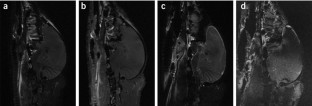

Many of the 5,500 threatened species of vertebrates found worldwide are highly protected and generally unavailable for scientific investigation. Here we describe a noninvasive protocol to visualize the structure and size of brain in postmortem specimens. We demonstrate its utility by examining four endangered species of kiwi (Apteryx spp.). Frozen specimens are thawed and imaged using MRI, revealing internal details of brain structure. External brain morphology and an estimate of brain volume can be reliably obtained by creating 3D models. This method has facilitated a comparison of brain structure in the different kiwi species, one of which is on the brink of extinction. This new approach has the potential to extend our knowledge of brain structure to species that have until now been outside the reach of anatomical investigation.

Corfield, J., Wild, J., Cowan, B. et al. MRI of postmortem specimens of endangered species for comparative brain anatomy. Nat Protoc 3, 597–605 (2008). https://doi.org/10.1038/nprot.2008.17